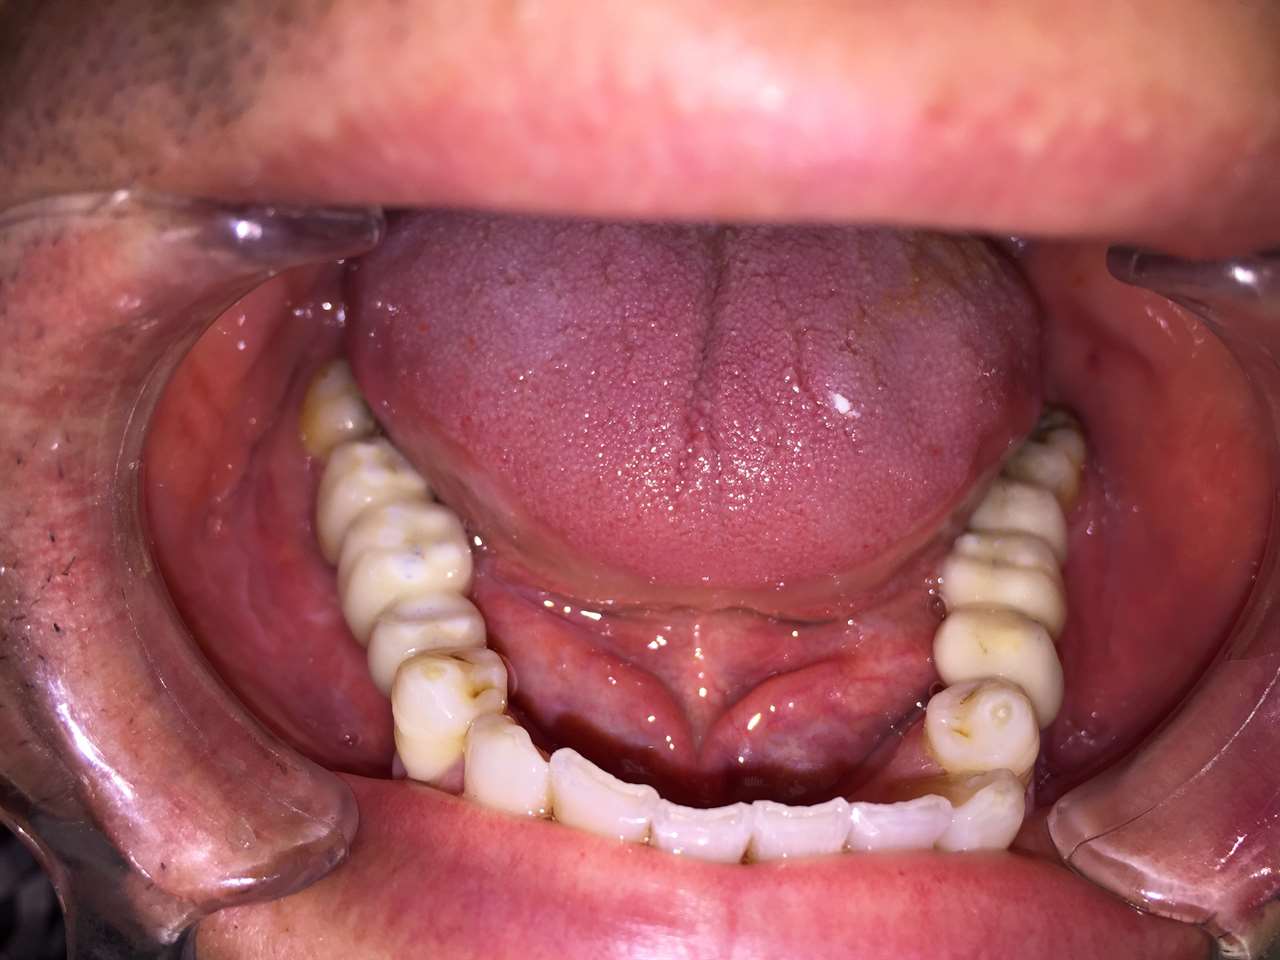

Alsó állcsont teljes rehabilitációja 72 óra alatt

Alsó állcsont teljes rehabilitációja 72 óra alatt, azonnal terhelhető implantátumokkal súlyos paradontitisben szenvedő dohányzó páciens esetében. Az alsó állcsont fogai mind mozogtak az előrehaladott fogágypusztulás miatt.

A fogakat eltávolítottuk, a gyulladt, fertőzött csontot kitakarítottuk, kifertőtlenítettük, majd azonnal implantáltunk.

Svájci, IHDE márkájú, azonnal terhelhető implantátumokat helyzetünk be, és ezekre harmadnapra rögzített, hosszútávú, fémvázas, esztétikus műanyaggal leplezett hidat ragasztottunk be.

Ezt az ideiglenes hidat a sebek gyógyulása miatt használjuk, de tartóssága miatt véglegesként is használható. A legtöbb esetben, ahogy itt is, 6 hónap múlva porcelán hídra cseréljük, a teljes gyógyulás után.